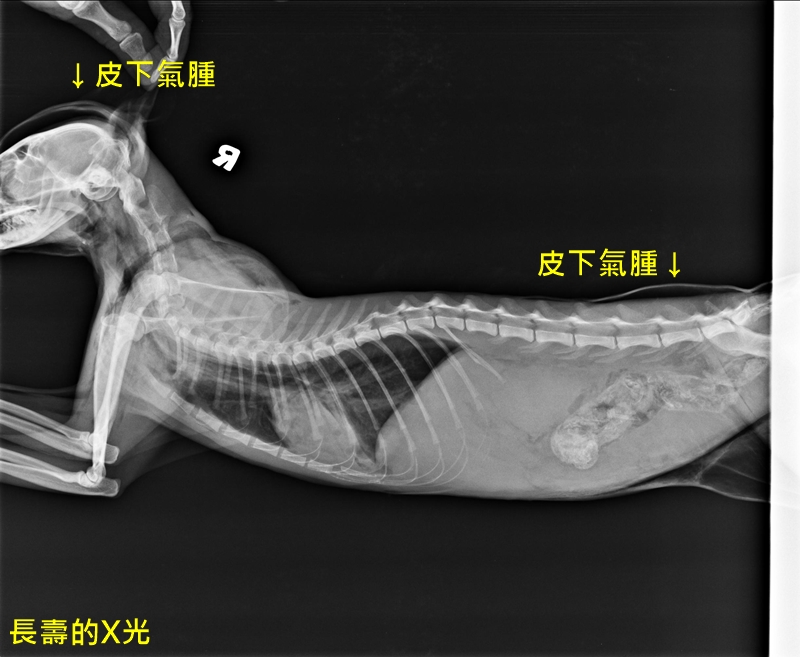

這畫面太驚悚,我真的超怕!但是黑白貓不斷對我大叫,顯然還活著。總之先把他撈進塑膠袋,先送到醫院再說吧。在X光掃描下,發現肋骨的 5、6、7、8、12、13 骨折,總共 6 根肋骨斷掉,骨盆骨折,肺氣腫及皮下氣腫,心肺功能問題,腹部可能有內出血。抽血檢查發現貧血,白血球升高到 5 萬左右,伴隨胰臟炎、肝指數升高,此外還有上呼吸道問題。醫師希望先觀察三天,如果能撐過危險期,再看要不要治療。貓咪當天有自行排尿,算是個好消息。從檢查結果來看,貓咪應該是左側被車撞上。

身上包的迷彩彈性繃帶,是為了治療皮下氣腫,沒有包到的肚子脹得很大。